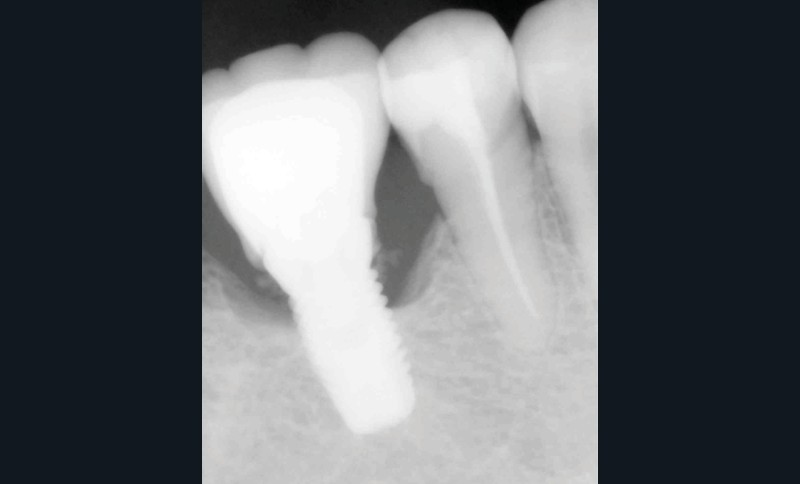

La seconde complication, plus grave, est le risque d’oublier des excès de ciment au niveau sous gingival. Ces derniers sont la cause principale avérée des péri-implantites et des pertes osseuses (fig. 2). Il est donc nécessaire de prendre toutes les précautions pour limiter au maximum ce risque.

Il est indispensable de faire un contrôle radiographique pour vérifier l’absence de ciment au-delà du joint. Cependant, la radiographie ne permet pas de mettre en évidence les excès vestibulaires ou linguaux, cachés par l’implant ou le pilier.

Cela implique d’utiliser un matériau suffisamment radio-opaque. La littérature préconise sur ce point l’emploi de ciments au carboxylate ou à l’oxyde de zinc. Ils présenteraient la meilleure radio-opacité [3].